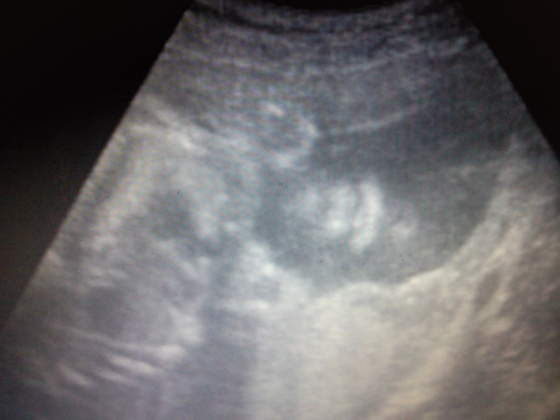

Nasze fasolki na USG

Zdj&#281;cie1257..jpgZdj&#281;cie1264..jpgZdj&#281;cie1258..jpg

a to nasz córcia w 27 tyg jakie ma sliczne usteczka:-D:-D:-D